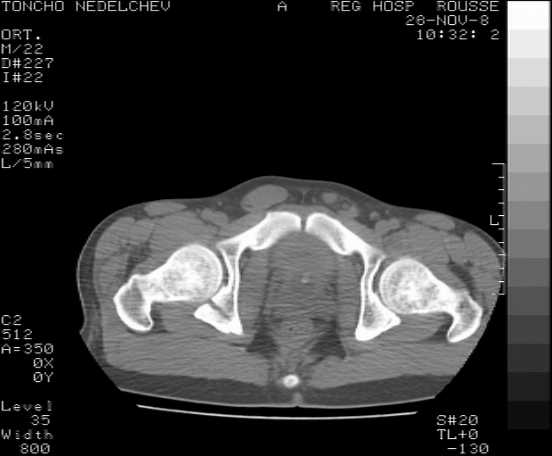

The details of the fracture are not so clear from the images sent...would you be able to send along an AP and Judet images as well as some additional axial images above and below the joint?

I’m not so sure that your patient has a Tr+PW pattern based on the images sent...maybe the fracture’s exact name won’t matter in the long run, but it’d be great to see enough images to make an accurate comment.

Here are some more axial images. What is your opinion as for the timing of the operative treatment?